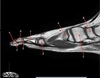

What is letter A?

A

CORACOID PROCESS

How well did you know this?

1

Not at all

2

3

4

5

Perfectly

Q

What is letter B?

DELTOID MUSCLE